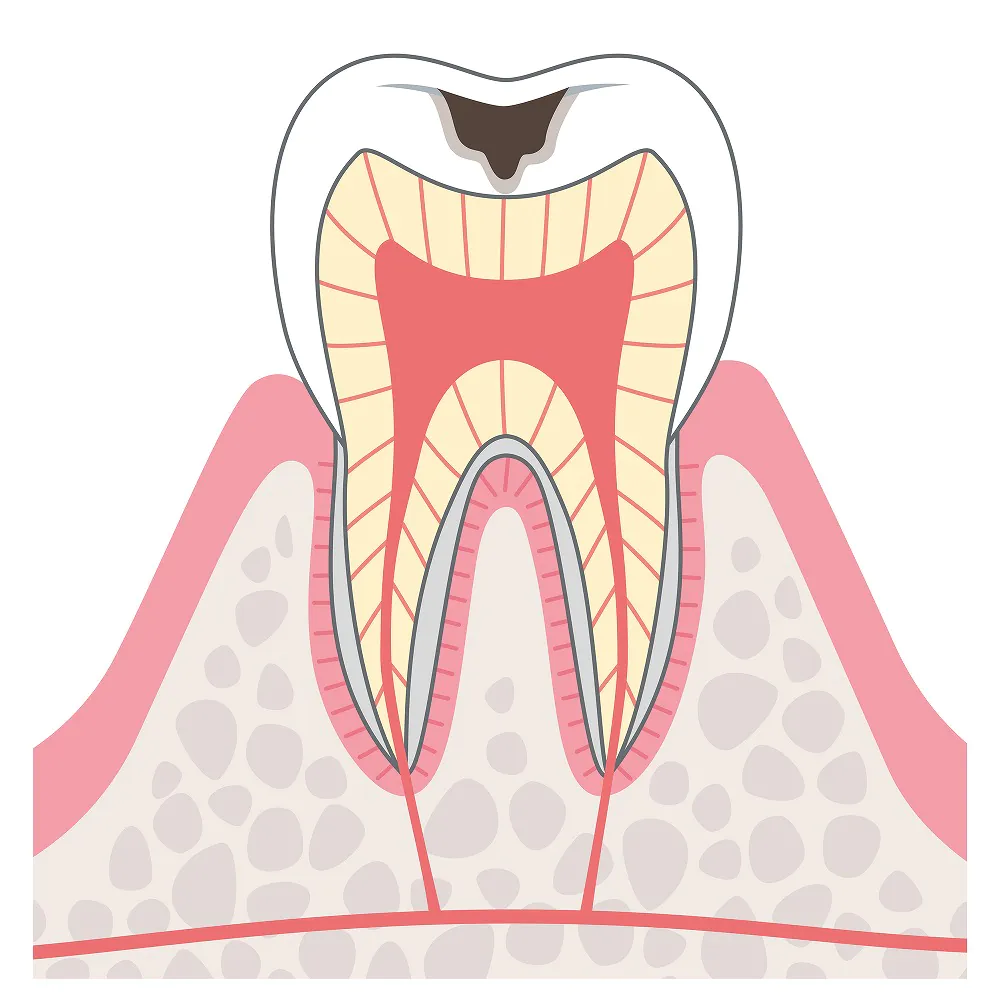

C2:痛みやしみるなどの症状が現れる

むし歯が歯の内部の象牙質にまで達した状態です。歯の黒い範囲が広くなるとともに、痛みやしみるなどの症状が現れます。進行すればするほどに歯の神経に近くなるため、それだけ症状が現れやすくなります。

むし歯が歯の内部の象牙質にまで達した状態です。歯の黒い範囲が広くなるとともに、痛みやしみるなどの症状が現れます。進行すればするほどに歯の神経に近くなるため、それだけ症状が現れやすくなります。

C3:激しい痛みが生じるむし歯

むし歯が歯の神経に達した状態です。強い炎症が起きて激しい痛みが生じるため、この段階で歯医者に駆け込む方が少なくありません。

むし歯が歯の神経に達した状態です。強い炎症が起きて激しい痛みが生じるため、この段階で歯医者に駆け込む方が少なくありません。